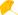

患者男,60岁。因"咳嗽、气短3周,加重2 d"于2017年11月17日入住我院呼吸内科。患者于入院前3周左右劳累后开始出现咳嗽,为干咳,伴有气短,无明显咳痰,无鼻塞、流涕等上呼吸道感染症状,无发热。患者未予重视,仅自行服用止咳糖浆治疗,症状未缓解。入院前2天,患者自觉症状加重,于上海交通大学医学院附属新华医院呼吸科门诊就诊,查胸部CT平扫(2017年11月15日)提示:前纵隔占位,右侧胸腔积液,伴右肺下叶不张(图1)。为进一步诊治,收治入院。否认药物食物过敏史、手术外伤史、传染病史。否认既往其他系统病史。有吸烟史40余年,每日10支。无特殊职业史。入院查体:血压120/80 mmHg(1 mmHg=0.133 kPa)。意识清楚,呼吸稍促。全身皮肤未见黄染,无瘀点、瘀斑。浅表淋巴结未触及肿大。左肺呼吸音稍粗,右下肺呼吸音减弱,两肺未闻及干湿啰音和胸膜摩擦音。心率126次/min,律齐。腹平软,无压痛、反跳痛及肌卫,肝脾肋下未触及。双下肢无水肿。生理反射存在,病理反射未引出。

图1 入院前胸部CT平扫提示前纵隔占位,右侧胸腔积液 A:纵隔窗;B:肺窗